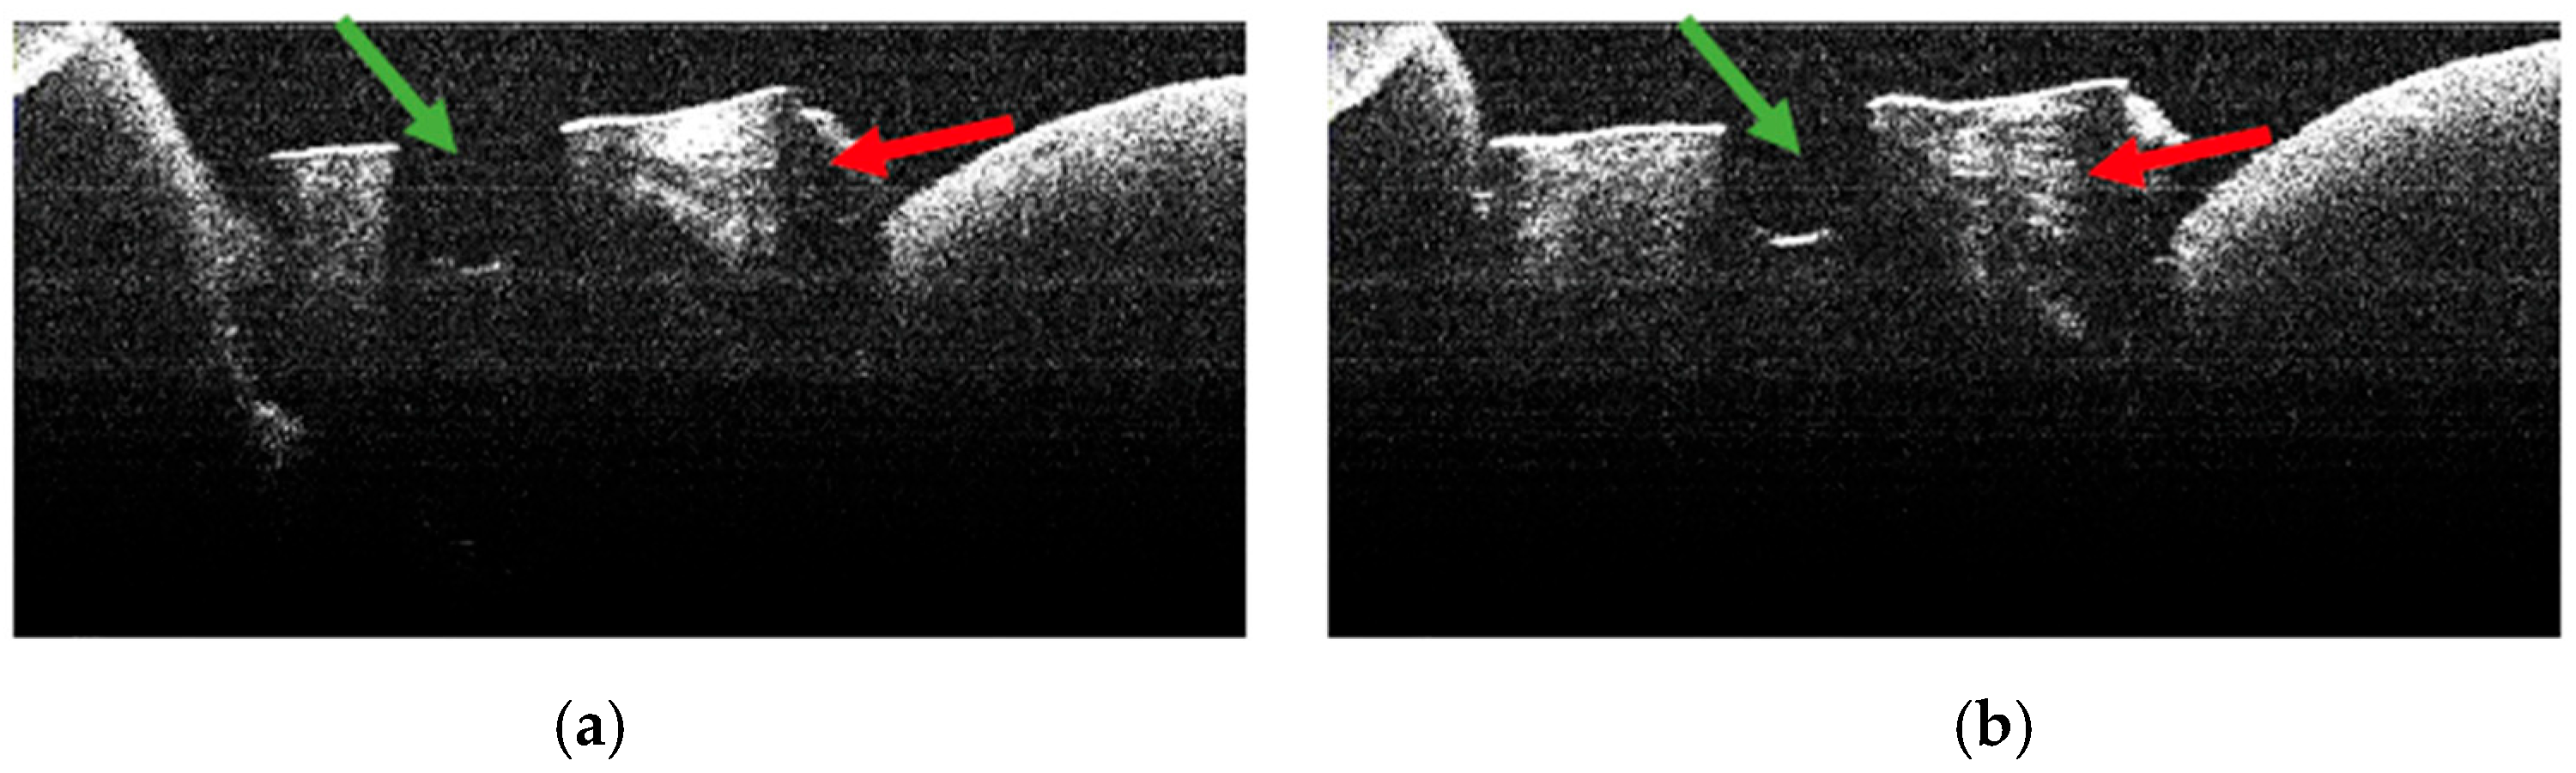

3.2. Defining OCT Signatures: Alterations vs. Artefacts

3.4. OCT Examination of Specimens from Group A

3.5. OCT Examination of Specimens from Group B